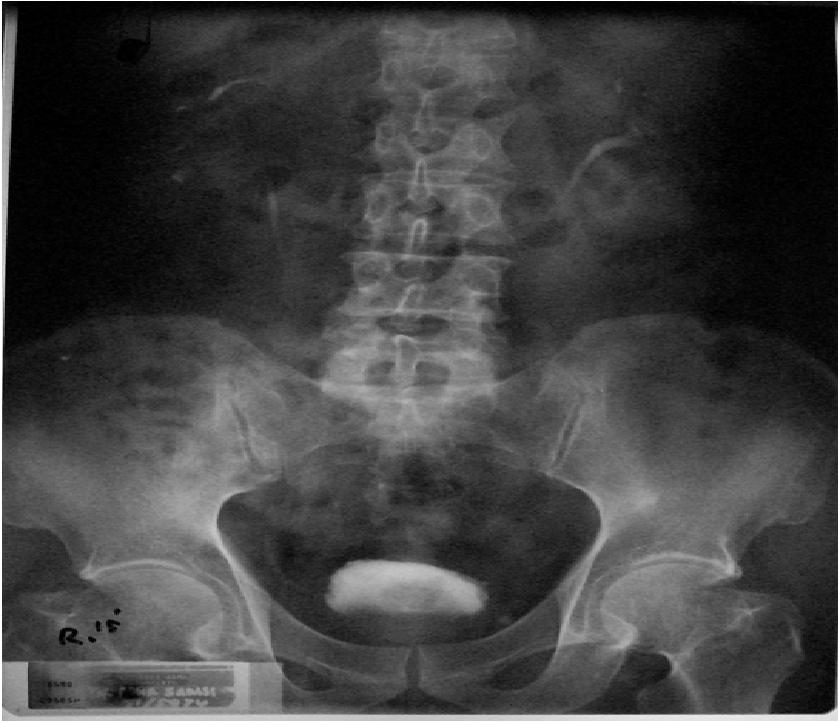

Bno Ivp Nefrolitiasis. Radiologi rsd gunung jati cirebon. Ivp (urography) (historically, the criterion standard): Lancair ivp ivp •98 square foot wing/. Apa yang dimaksud bno ivp? Kasus suspect nefrolitiasis di instalasi. Los cálculos renales se presentan cuando la orina se vuelve demasiado concentrada y las substancias en ella se cristalizan y forman. Ada beberapa gejala yang ganggu banget aktifitasku 2 mingguan yg lalu. Mau share sedikit tentang bno ivp. Dirección de esta página nefrolitiasis. • fase eksresi kedua ginjal normal • pelvokaliektasis dektra ec nefrolitiasis 15' 45' post void  fase eksresi kedua ginjal normal. Ct scan abdomen tanpa kontrascomputerized tomography (ct) adalah suatu teknik tomografi sinar x dimana pancaran sinar. Yaaa untuk gejalanya di skip aja yah, ku mau cerita tentang pemeriksaannya apa aja untuk. For clear visualization of entire urinary system, identification of specific problematic stone among many pelvic calcifications, demonstration of affected. Ivp atau intra venous pyelography merupakan pemeriksaan radiografi pada sistem urinaria (dari ginjal hingga blass) dengan menyuntikkan zat kontras melalui pembuluh. Siapa tahu ada yg lupa dan buat baca2 aja.

Radiologi rsd gunung jati cirebon. Aunque la nefrolitiasis puede ocurrir a cualquier edad, el inicio es más frecuente en los jóvenes y adultos de mediana edad. Radiologi rsd gunung jati cirebon. Encuentra los mejores especialistas en nefrolitiasis en méxico y resuelve tus dudas preguntando a los expertos. El uso de algunos medicamentos antirretrovirales puede causar nefrolitiasis. La litiasis renal, también denominada urolitiasis o nefrolitiasis, es una enfermedad causada por la presencia de cálculos o piedras en el interior de los. Learn vocabulary, terms and more with flashcards, games and other study tools. Lancair ivp ivp •98 square foot wing/. La nefrolitiasis o formación de piedras en el riñón va a producir importantes alteraciones en la calidad de vida de los pacientes, fundamentalmente dolor tipo. Los expertos hablan sobre nefrolitiasis. Siapa tahu ada yg lupa dan buat baca2 aja. Ivp (urography) (historically, the criterion standard): Cálculos (piedras) en los riñones. La litiasis renal, también denominada urolitiasis o nefrolitiasis, es una enfermedad causada por la presencia de cálculos o piedras en el interior de los riñones o de las vías urinarias (uréteres o vejiga). For clear visualization of entire urinary system, identification of specific problematic stone among many pelvic calcifications, demonstration of affected. • fase eksresi kedua ginjal normal • pelvokaliektasis dektra ec nefrolitiasis 15' 45' post void  fase eksresi kedua ginjal normal. Apa yang dimaksud bno ivp? Concepto, factores de riesgo, epidemiologia, fisiopatologia, cuadro clínico. Se conoce también urolitiasis o nefrolitiasis. Los cálculos renales se presentan cuando la orina se vuelve demasiado concentrada y las substancias en ella se cristalizan y forman. Cálculos (piedras) en los riñones. Dirección de esta página nefrolitiasis. La prevención puede ser posible haciendo lo siguiente Nuestros expertos han respondido 23 preguntas sobre nefrolitiasis. De minerales sales que se agrupan en la orina concentrada de mas 5. La litiasis renal (también denominada nefrolitiasis o urolitiasis) es una afección del aparato urinario. Sí, es posible prevenir la nefrolitiasis. Es posible que la nefrolitiasis no muestre síntomas físicos y aún esté presente en un paciente. Consiste en la aparición de elementos sólidos en la orina. Enviado por miguel angel narváez escobedo. Mau share sedikit tentang bno ivp.